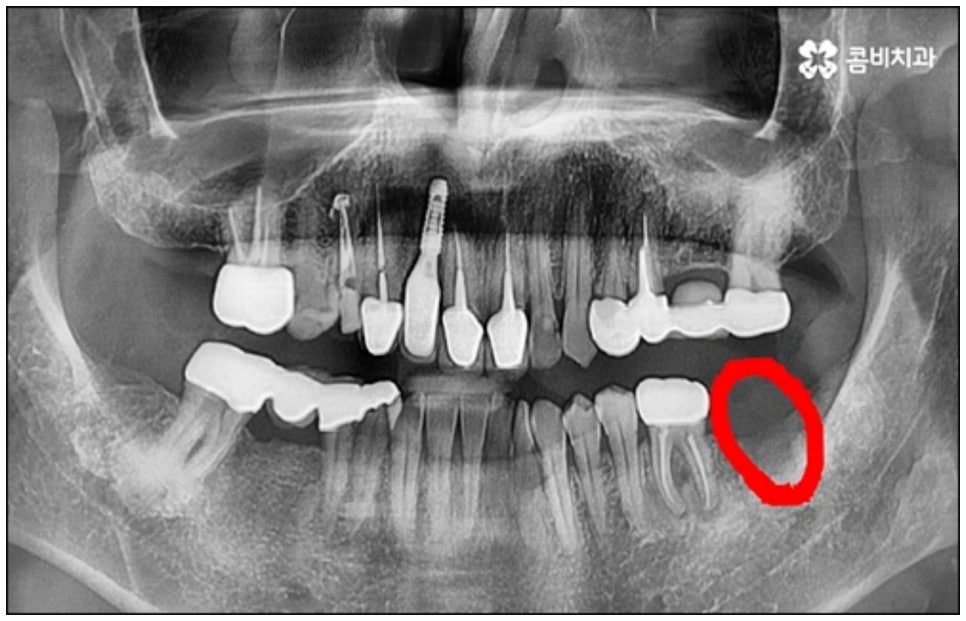

다만 누구나 당일임플란트 시술이 가능한 것은 아니기 때문에 주의가 필요한데요, 위에서 언급했던 사전 치료가 필요한 경우와 같이 바탕이 되는 잇몸 건강이 좋지 않다면 바로 식립을 진행할 수 없기 때문에 시술 전 정밀 검사를 통해 꼼꼼하게 진단을 하고 각자의 상황에 대해 담당 의료진과 충분하게 상담을 해 보시는 것이 중요하다고 할 수 있습니다.

예를 들어서 오랜 치주염으로 퇴축이 진행되어 잇몸이 이미 많이 내려앉은 경우, 심한 치아 뿌리 염증으로 잇몸뼈가 상당부분 녹은 경우, 노화나 지병으로 인해 골밀도가 낮고 잇몸뼈가 약해져 지지가 어렵거나 쉽게 부서지는 등 뼈의 상태가 양호하지 못한 경우 등에 있어서는 발치 후 즉시 임플란트를 식립하는 방식이 적합하지 않으며 치아가 한꺼번에 여러개 손상된 경우에도 6~8주 정도의 시간을 두고 무리하지 않게 단계적으로 식립하는 것이 혹시 모를 부작용을 막고 장기적인 안정성을 높이는 방법이라고 할 수 있어요.

또한 한 번 식립된 인공 치근이 뼈조직과 골융합되고 난 다음에는 그 위치와 방향을 수정하기 어려운 만큼 혹시 모를 부작용이나 재수술 위험 없이 임플란트 치아를 사용할 수 있도록 안정성이 검증된 정품 재료를 사용하고 있는지, 잇몸 상태와 구강 구조를 세밀하게 체크할 수 있는 3D CT와 같은 정밀 검진 장비를 활용하는지 등등을 함께 꼼꼼하게 체크해 볼 필요가 있어요. 그리고 언급했던 것처럼 사후 관리 역시 임플란트 수명에 큰 영향을 주니 철저한 케어 시스템을 갖추고 임플란트 유지 관리를 도와주는 치과에서 진행하는 것 역시 중요하다고 할 수 있습니다.